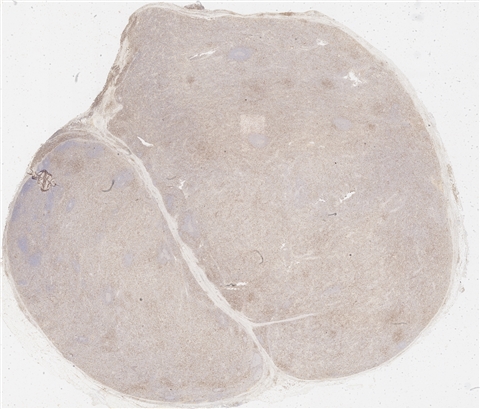

案例3 (6862)

性别:       年龄:65

患者详情: 患者3月余前在当地社区卫生服务中心体检发现血肌酐升高(109.8umo/L),无明显尿量减少,无颜面下肢浮肿无腰酸腰痛,无肉眼血尿,无关节疼痛,无皮疹红斑,开始未重枧及进一步诊治。10余天前患者到中山医院复查生化提示“肌酐200umol/L、尿素7.3mmol/L、尿酸637umol/L、白蛋白34g/L、球蛋白66g/L、蛋白电泳β15.0%、蛋白电泳Y42.6%”,同时其它检查提示“血lgG4 54.20g/L”。 CT:纵隔及双侧腋下多发肿大淋巴结,肺动脉干稍増粗,主动脉硬化,扫及双肾饱满,后腹膜发淋巴结。 PET-T:全身多区域淋巴结肿大、双侧泪腺、双侧颌下腺及胰腺体尾部饱满、双肾实质肿胀,左侧头皮局部增厚,伴FDG代谢增高,鼻咽顶后壁及前列腺腺体FDG代谢增高,上述病灶首先考虑IgG4相关性疾病所致可能,建议暖股沟淋巴结活检病理明确除外淋巴瘤。

大体所见: 结节一枚3*3*2cmA-C。

医院: 上海交通大学医学院附属仁济医院